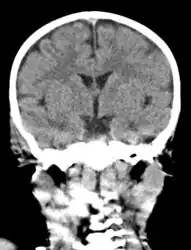

The diagnosis of mastoiditis is clinical—based on the medical history and physical examination. Imaging studies provide additional information; The standard method of diagnosis is via MRI scan although a CT scan is a common alternative as it gives a clearer and more useful image to see how close the damage may have gotten to the brain and facial nerves. Planar (2-D) X-rays are not as useful. If there is drainage, it is often sent for culture, although this will often be negative if the patient has begun taking antibiotics. Exploratory surgery is often used as a last resort method of diagnosis to see the mastoid and surrounding areas.[7][8]

Acute mastoiditis -

CT scan: Otitis media (simple arrow) and mastoiditis (double arrow) of the right side (left side in image). The external auditory canal is partially occupied by suppuration (triple arrow). 44-year-old woman